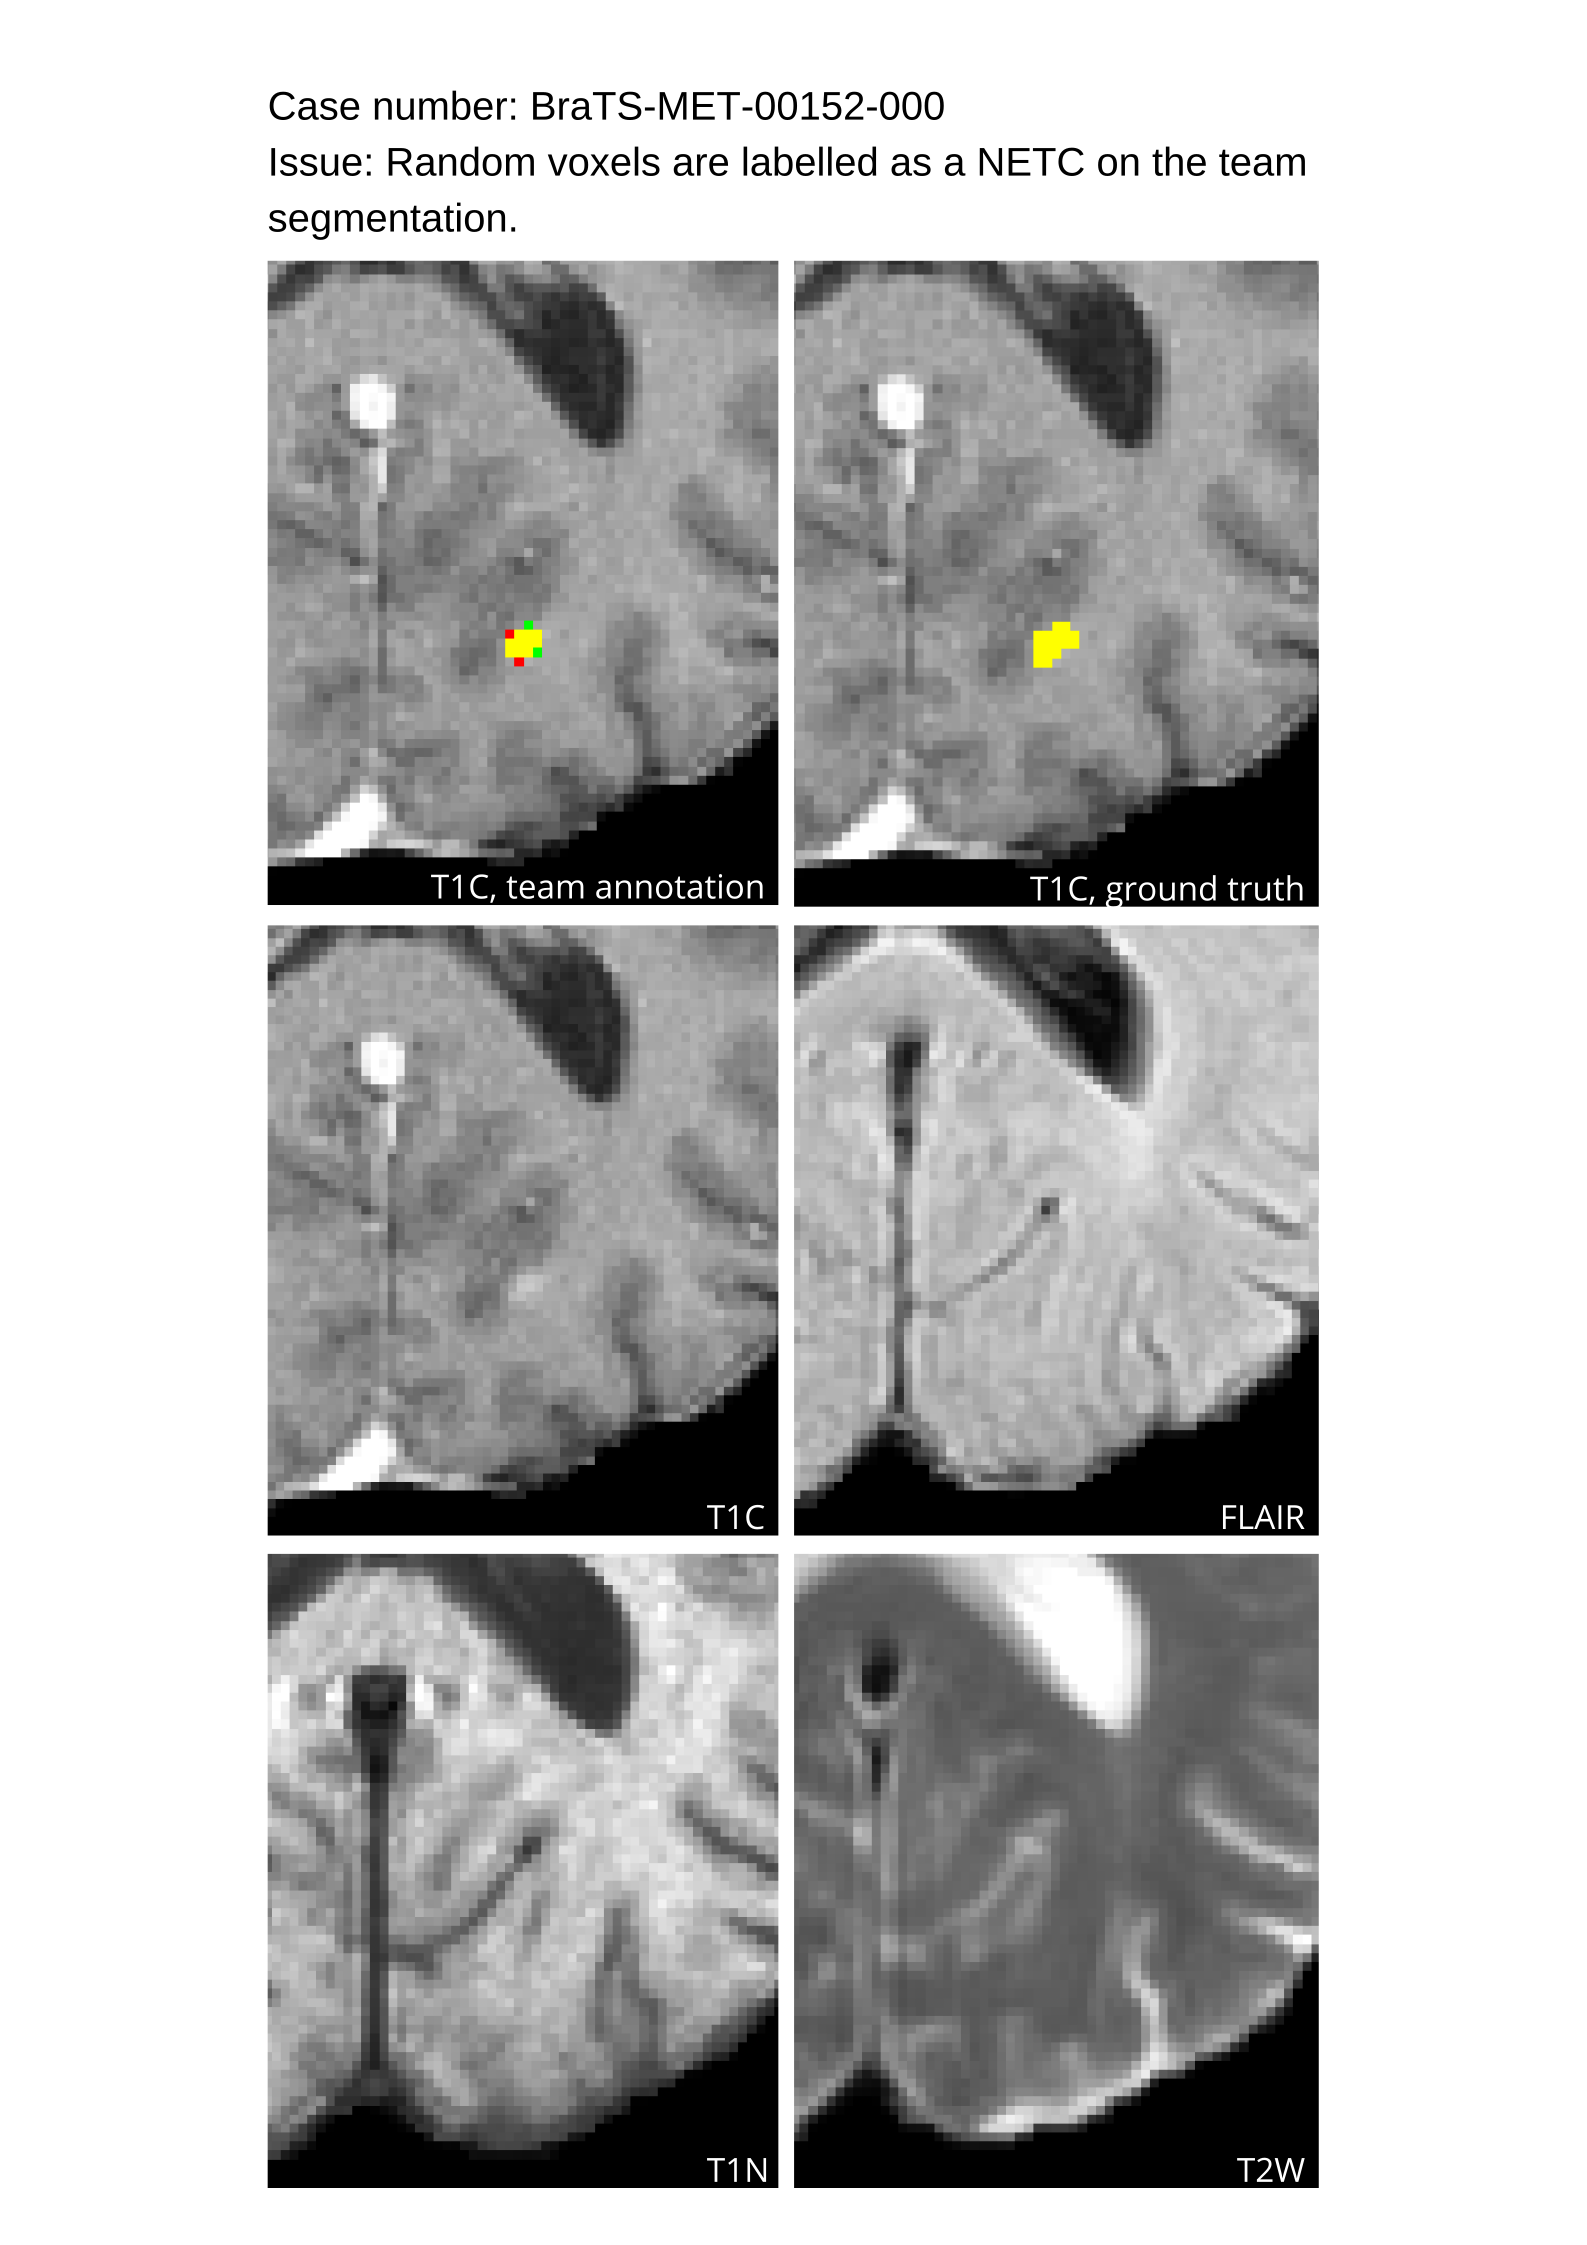

All pre-segmentations from the three models, along with fused segmentations, were provided to the annotators. Subtraction images, in which the non-contrast T1 sequence is digitally subtracted from the post-contrast T1 sequence, were also provided to aid in the annotation refinement process. Annotations were performed by a diverse group of more than 150 student annotators and volunteer neuroradiology experts, under the supervision of annotator coordinators (A.J. and K.K.). Cases requiring re-annotation due to incompleteness were identified and returned for correction. During the process of annotation, the trainees participated in group reviews of cases, asked questions, and attended lectures by expert imagers. Completed student annotations were then reviewed by a pool of 52 experienced board-certified attending neuroradiologists (approvers) recruited by the American Society of Neuroradiology, ensuring quality control and uniformity with the SRI24 atlas standards.

Approvers reviewed the volunteer annotations and either approved the case or returned it to students for re-annotation. Additionally, a QC process was implemented, which included removing all random voxels and any voxels outside the brain mask, ensuring all images had the same parameters (space, orientation, and origin) as the SRI24 atlas, and verifying the presence of all segmentations and segmentation masks are in the folder with original NIfTI images.

4.9 Common Errors of Automated Segmentations

Based on observations from previous BraTS challenges, common errors in automated segmentations were identified. The most typical errors in the current challenge included:

1. 1.

Automated algorithms missing small metastases. Enhancing metastasis was fused using the minority voting algorithm to aggregate all enhancing tumor voxels identified by the three algorithms. However, many small metastases were missed and were manually segmented by neuroradiology attendings.

2. 2.

Segmentation of white matter changes from microvascular disease. Peritumoral edema segmentations were checked by neuroradiology attendings and modified.

3. 3.

The segmentation of non-enhancing lesions that have intrinsic T1 hyperintensity. Voxels with intrinsic T1 hyperintensity were manually removed from ET segmentations.

These insights led to specific adjustments in the annotation process to enhance accuracy.